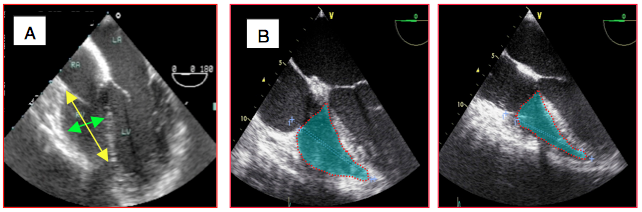

A cause de sa forme en croissant enroulé autour du VG, le VD présente normalement une surface plus petite que celle du VG par un facteur de 0.6 dans tous les plans de coupe. En 4-cavités, une taille identique des deux ventricules signe déjà une dilatation du VD ; une taille du VD supérieure à celle du VG correspond à une dilatation sévère. La longueur du VD ne doit pas excéder les 75% de celle du VG. L'apex du cœur est normalement formé par celui du VG. Lorsque le VD se dilate, son extrémité dépasse celle du VG; l'apex est alors celui du VD (Figure 25.209).

Figure 25.209 : Tailles comparatives des deux ventricules. A: normalement, le VD est plus petit que le VG dans tous les plans de coupe; l'apex du cœur est formé par le VG (flèche). B: en cas de dilatation droite, l'apex est formé par celui du VD (flèche verte).